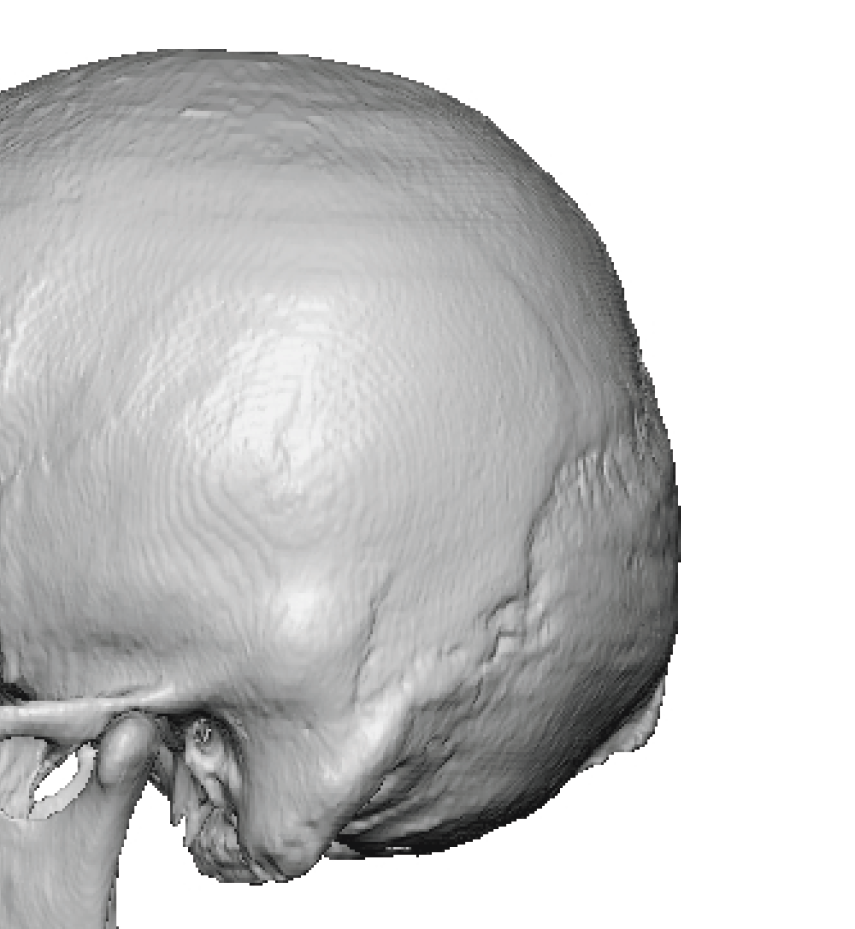

Severe narrowing skull deformity from prior sagittal craniosynostosis repair as an adult.

Complete replacement of entire skull by a custom implant with temporal fat injections.

Severe narrowing skull deformity from prior sagittal craniosynostosis repair as an adult.

Complete replacement of entire skull by a custom implant with temporal fat injections.